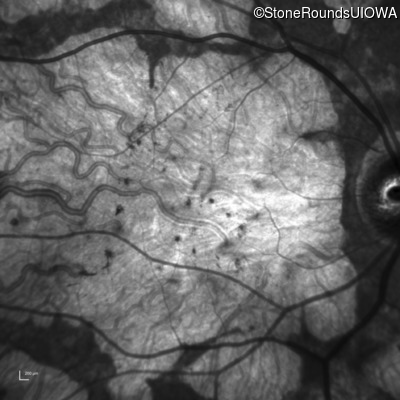

| AR Stargardt Disease | ABCA4 | Cys205Phe TGC>TTC | Gly863Ala (G)GA>(G)CA | AR |